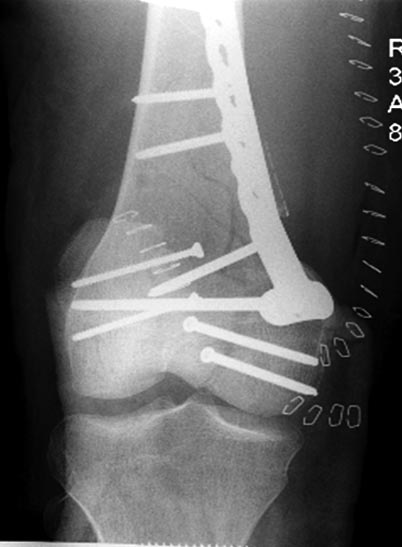

Раны в области коленного сустава и на плече до сих пор чистые, остаются открытыми. Отсутствует признаки инфекции, решили превратить недостаток в преимущество, т.е. фиксировать через открытые раны пластинами.

На 9й день фиксация дистального бедра, где фрагмент Hoffa и вертикальный перелом надколенника, зафиксированы винтами.